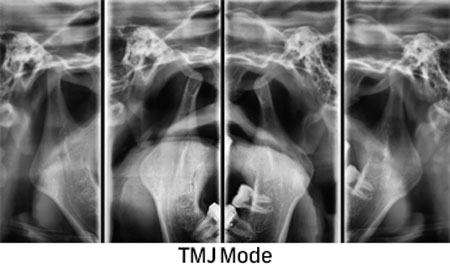

For an exact diagnosis and a target-oriented treatment it is necessary to look inside the tooth. EDG offers wide range of 2D and 3D CBCT Digital Radiography.

We use the newest technology to enable a precise treatment for our patients through imaging methods.